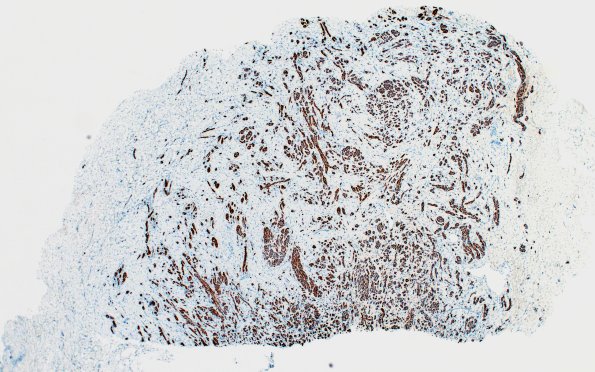

A low magnification image of the area 23A1 deeper into the block showing numerous axons gathered into mini-fascicles. (NF IHC)